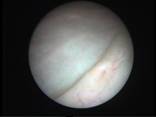

Acute Scrotum